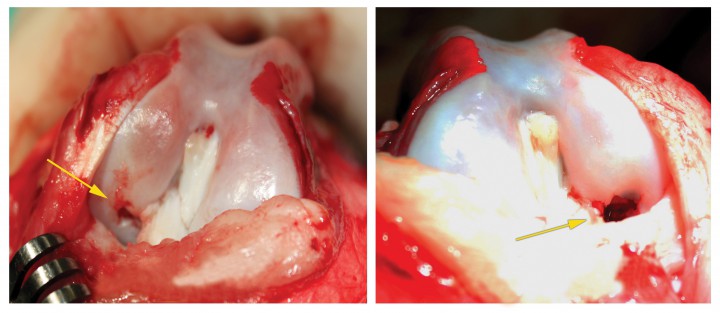

Ambas lesiones osteocondrales (Fig. 4) fueron tratadas simultáneamente, mediante la técnica de la OATS, en la misma intervención quirúrgica[ Cook JL, Hudson CC, Kuroki K. Autogenousostechondral grafting for treatment of stifle osteochondrosis in dogs. Vet Surg 2008; 37 (4):311-21. [PubMed] ] (Single use OATS set ArthrexTM, de 6 mm, número de referencia AR-8981-06S) (Fig. 5). La realización de esta técnica permite y facilita la reparación de defectos de un diámetro de 6, 8 o 10 mm a través de cilindros de cartílago hialino desde una adecuada zona donante que, en casos de lesiones femorales, se corresponde con la zona dorsolateral del labio de la tróclea femoral. Para ello, se crea una cavidad receptora, de tamaño y profundidad adecuada en el defecto condral, que acepte el injerto del donante.

<p>Imagen macroscópica del cóndilo lateral después de la artrotomía. (A) Imagen del fémur derecho mostrando la lesión (flecha amarilla). (B) Imagen del fémur izquierdo mostrando la lesión (flecha amarilla).</p>

Imagen macroscópica del cóndilo lateral después de la artrotomía. (A) Imagen del fémur derecho mostrando la lesión (flecha amarilla). (B) Imagen del fémur izquierdo mostrando la lesión (flecha amarilla).